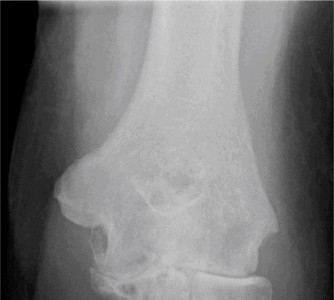

Manage a patient after total shoulder arthroplasty? CASE 18 Dr. Anna Cohen-Rosenblum A 55-year-old female with a history of rheumatoid arthritis diagnosed at age 40 presents to your clinic complaining of 3 years of right shoulder pain acutely worsening over the past week to the point that she is unable to reach for objects from high shelves and needs help getting dressed in the morning. She also notes recent intermittent fevers and severe pain in her left hand and decreased range of motion of the fingers. She participated in a 6-week course of physical therapy last year prescribed by her rheumatologist which provided no relief. She receives an injection of a TNF-alpha inhibitor every 8 weeks. Physical examination reveals

tenderness to palpation, swelling and warmth about the left shoulder with decreased range of motion throughout. Her left hand is neurovascularly intact with ulnar deviation of the fingers and severe limitation of range of motion. Imaging of the right shoulder is shown in Figure 2–52.

Figure 2–52

What is the most appropriate next step in diagnosis/treatment?

The correct answer is (D). In a patient with rheumatoid arthritis, the most likely diagnosis is inflammatory arthropathy involving the shoulder, however, the presence of fevers and acutely worsening pain with swelling and warmth on physical examination necessitates a workup for septic arthritis. MRI of the shoulder (Answer A) might be indicated in the future if there is question about rotator cuff integrity in the setting of a decision to perform a total shoulder arthroplasty, but not at the time of initial diagnosis. Subacromial steroid injection (Answer B) would not be indicated in a patient in whom septic arthritis is suspected. Physical therapy (Answer C) would be helpful for conservative management of inflammatory

The correct answer is (C). It is important in patients with rheumatoid arthritis to address other sources of pain that might impede the postoperative rehabilitation process. This patient will be unable to use her right, dominant hand as effectively after shoulder surgery, and will be far more reliant on her left hand in the postoperative period. Since she has severe pain and deformity of the left hand, she should be evaluated by a hand surgeon to determine whether this issue might be addressed prior to her undergoing an operation on her shoulder. Choice A is incorrect not only because the left hand should be evaluated first, but because imaging of her right shoulder reveals severe erosion as well as osteopenia of the glenoid, which is a contraindication to total shoulder arthroplasty due to placement of the glenoid component. Choice B is incorrect only because of the timing with this patient; it is actually the most appropriate operative choice given her poor glenoid bone stock and relatively younger age. Choice D is incorrect as arthrodesis is more appropriate for patients with failed total shoulder arthroplasty, and end-stage rheumatoid arthritis (arthritis mutilans) complicated by septic arthritis.